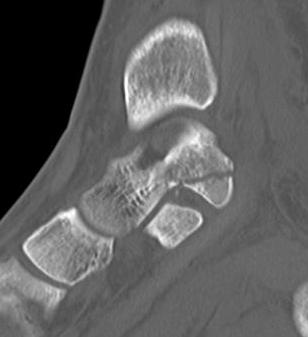

Fracture Sustenaculum Tali